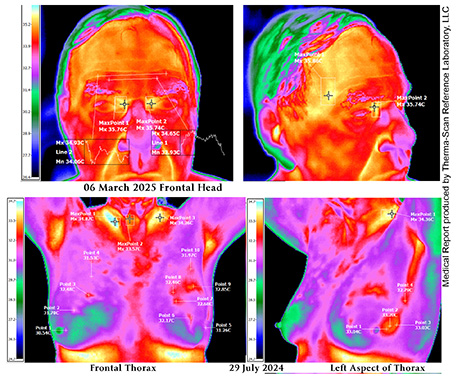

The science of MEDICAL THERMOGRAPHIC IMAGING has been significantly advanced through the integration of diagnostic infrared imaging technology and our partnership.with Therma-Scan™ Laboratory. With their award-winning scientific leadership that comports the scanned imaging output into quantitative medical reporting and lifesaving thermology solutions.

Thermology, also known as medical infrared imaging or digital infrared thermal imaging (DITI), is a non-invasive diagnostic tool that detects and measures subtle variations in skin surface temperature. This temperature data, which reflects the physiological activity of the body, is captured using highly sensitive infrared cameras. Unlike traditional imaging that focuses on structural abnormalities, thermology highlights functional changes, making it a valuable tool in the early detection and screening of conditions before they become anatomically evident. By analyzing thermal patterns and asymmetries across the body, clinicians can identify areas of inflammation, circulatory compromise, or nerve dysfunction with remarkable precision. Although not yet widely adopted as a standalone diagnostic method in mainstream medicine, thermology has gained increasing approval as an adjunctive tool in various specialties, including oncology, neurology, rheumatology, and pain management.

Thermographic imaging excels in identifying inflammatory processes by detecting hyperthermia associated with increased blood flow and metabolic activity. This is particularly valuable in screening for soft-tissue injuries, autoimmune conditions like rheumatoid arthritis, and neuropathic disorders, including complex regional pain syndrome (CRPS) and diabetic neuropathy. It is also effective in assessing musculoskeletal dysfunctions, including early-stage arthritis, by visualizing joint inflammation and temperature disparities. Thermology converts these temperature measurements into quantitative data that can be processed for clinical interpretation, often using pattern recognition algorithms and comparative mapping to track disease progression or response to treatment. As a radiation-free and contactless modality, thermology offers a safe, repeatable, and patient-friendly option for continuous monitoring of chronic conditions, enabling early intervention and improved clinical outcomes.